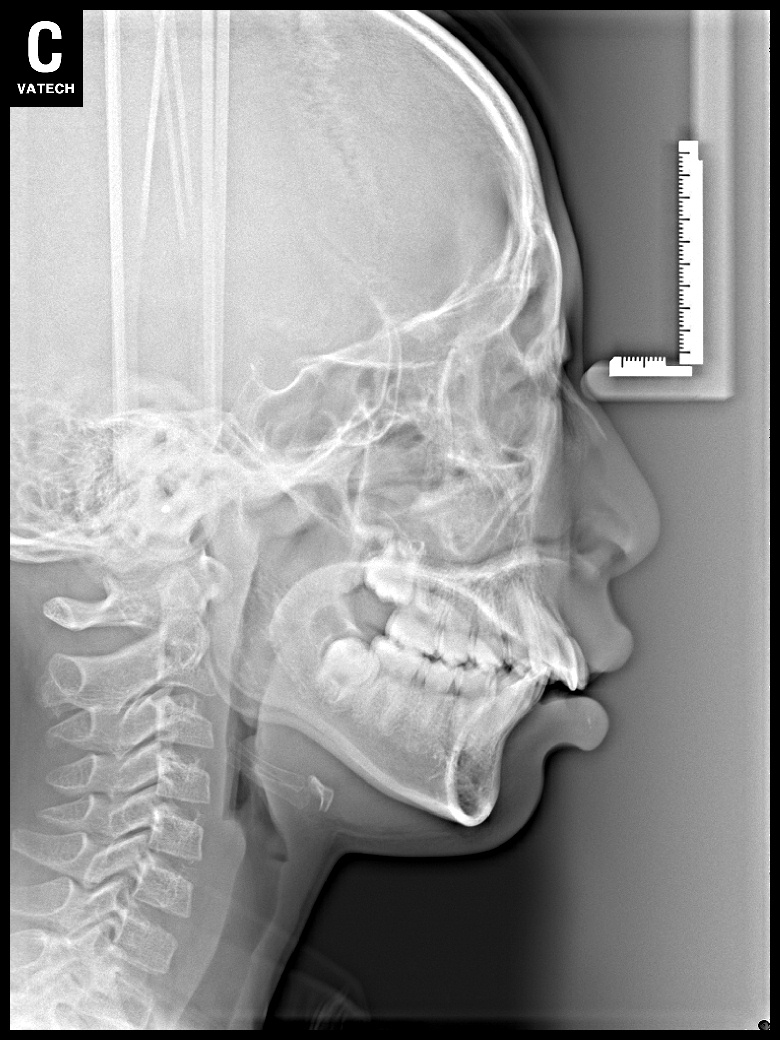

치료 후 사진입니다.